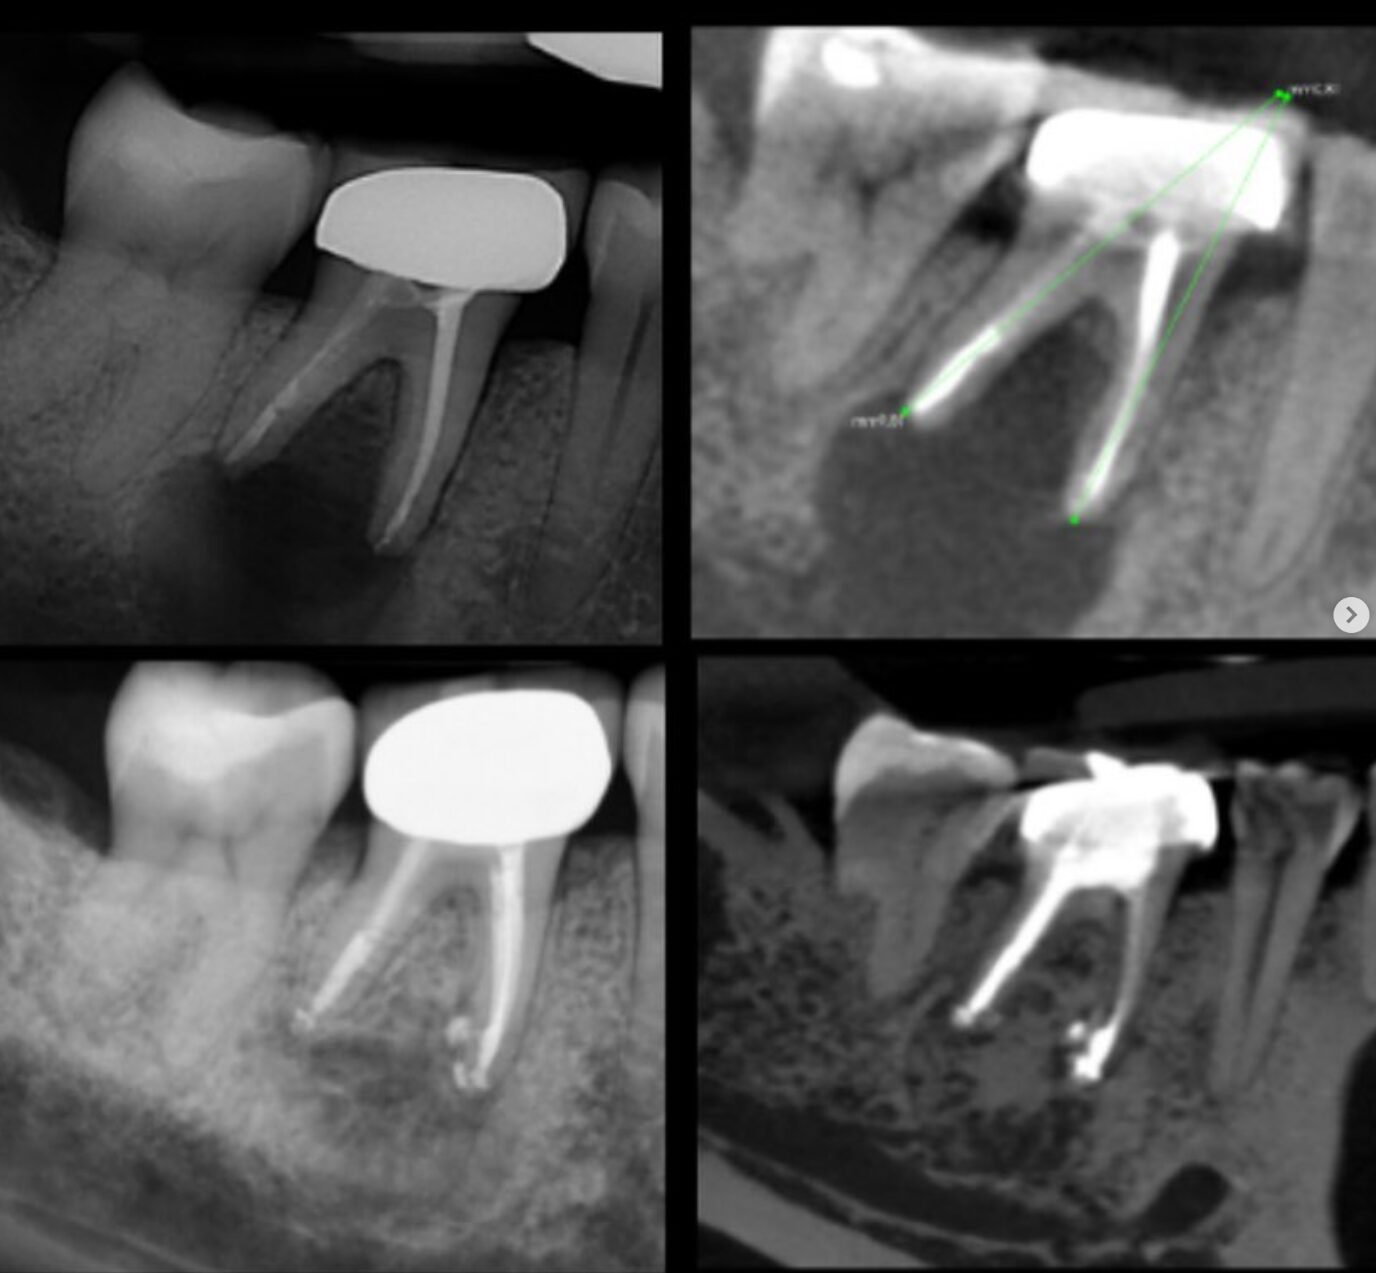

Case Studies

Discover all our case studies on Instagram by following @dana_point_endodontics and exploring our highlights or posts for in-depth insights and success stories!